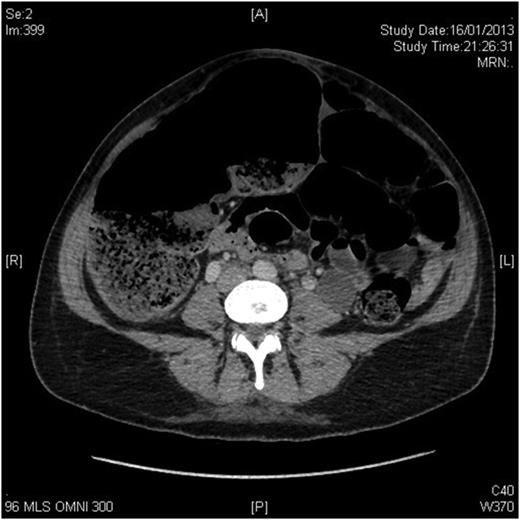

The patient, a 34-year-old female, developed symptoms consistent with pseudo-obstruction on Day 3 post-emergency Caesarean section, which was performed for foetal distress and possible placenta abruption. An abdominal X-ray was performed which showed a significantly dilated colon (Fig. 1), and the diagnosis of pseudo-obstruction was again confirmed on computer tomography (CT) scan of the abdomen which showed a caecum measuring 9.8 cm transversely (Fig. 2). Emergency colonoscopic decompression with the insertion of a flatus tube was performed and medical management, including cessation of opioids, anticholinergics and correction of electrolyte abnormalities, was commenced.

CT scan of the abdomen showing caecum measuring 9.8 cm transversely.